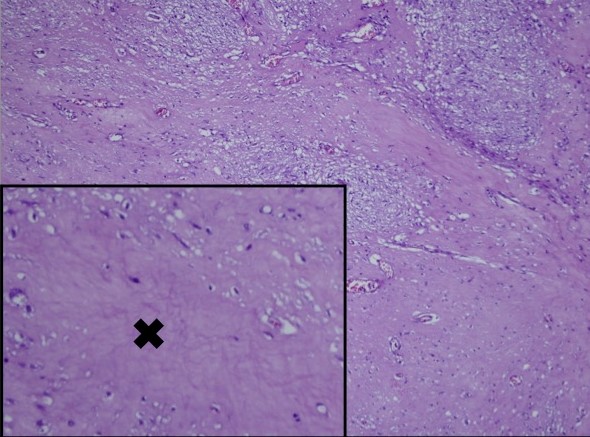

Microscopy showed nests and sheets of spindle cells infiltrating the muscularis propria. The cells have elongated nuclei, with fine chromatin, inconspicuous nuclei and moderate amount of pale eosinophilic and fibrillary cytoplasm (Figure 2). Mitotic count was 0 to 1 per 50 high power fields. However, areas of necrosis were seen in the specimen (Figure 3). The immunohistochemical stains done showed diffusely positive CD117 and DOG1, and negative for Desmin and S100, supporting the diagnosis of gastrointestinal stromal tumor (Figure 4). Based on the National Comprehensive Cancer Network (NCCN), it was stratified as having very low risk for progressive disease.

Figure 3. Gastric mass with areas of necrosis (x).